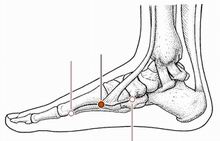

公孙穴

经穴名。出《灵枢·本输》。属足太阴脾经。足太阴之络穴。八脉交会穴之一,通冲脉。在足内侧缘,当第1跖骨基底的前下方,赤白肉际处。布有隐神经及腓浅神经分支,足背静脉网及跗内侧动脉。主治胃痛,呕吐,肠鸣,腹痛,泄泻,痢疾,腹胀,食不化,脚气等。直刺0.5-1寸。艾炷灸3-5壮;或艾条灸5-10分钟。

太白穴

经穴名。出《灵枢·本输》。属足太阴脾经。输(土)、原穴。在足内侧缘,当足大趾本节(第1跖趾关节)后下方赤白肉际凹陷处。布有隐神经及腓神经分支,足背静脉网,足底内侧动脉及跗内侧动脉的分支。主治胃痛,腹胀,呕吐,呃逆,肠鸣,泄泻,痢疾,便秘,脚气,痔漏等。直刺0.5-0.8寸。艾炷灸1-3壮;或艾条灸3-5分钟。